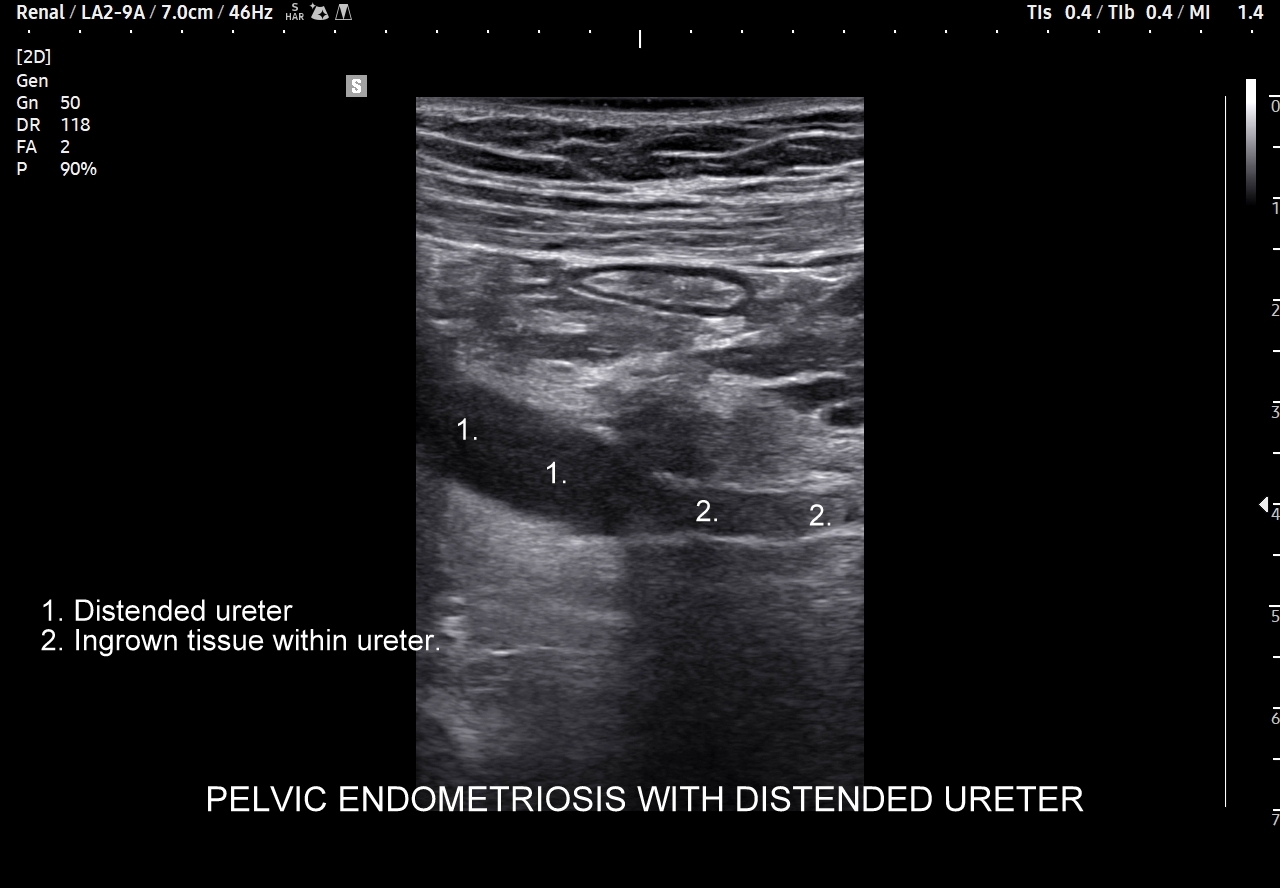

W badaniu USG ogniska endometriozy zwykle przyjmują formę hypoechogennych guzków i nieregularnych mas; mogą być niejednorodne echogenicznie i zawierać drobne obszary torbielowate; w trybie color-Doppler i MVI wykazują skąpe unaczynienie.

Na skanach w niniejszym artykule zaprezentowany jest przypadek endometriozy głębokiej w miednicy mniejszej z intraluminalnym nacieczeniem dystalnego odcinka moczowodu, jego całkowitą niedrożnością i wtórnym wodonerczem. Choroba w tak zaawansowanym stadium wykryta została przypadkowo w rutynowym przezbrzusznym badaniu USG jamy brzusznej. W ramach diagnostyki różnicowej przeprowadzone zostały badanie CT, MRI oraz ureterocystoskopia z pobraniem materiału do badania histopatologicznego, na podstawie którego postawiono rozpoznanie endometriozy.